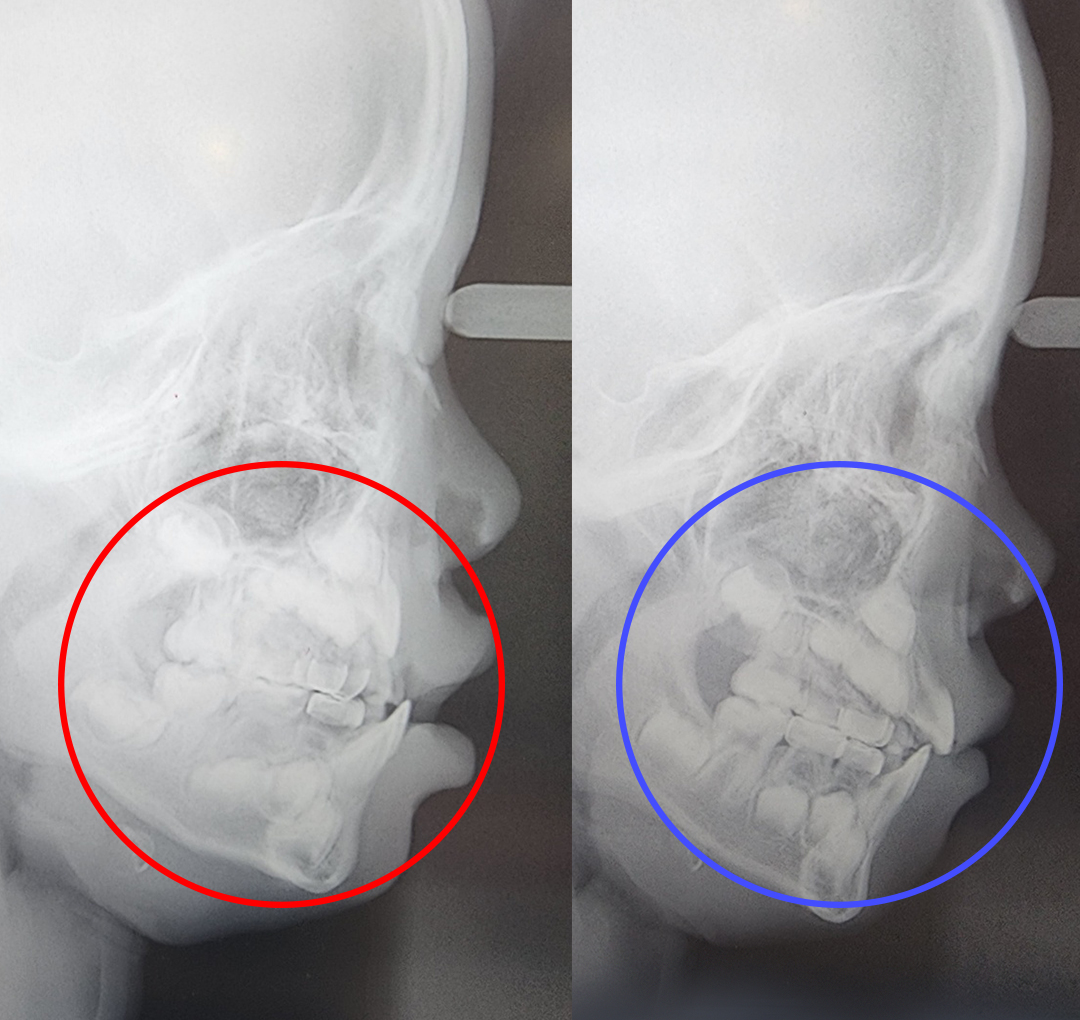

프랑켈장치 교정

어린이 3급 부정교합 & 프랑켈장치 교정

구호흡을 지속적으로 하게 되면 아래턱이 하방 성장하면서 아래 앞니가 위 앞니를 덮는 부정교합이 될 수 있습니다.

프랑켈장치 교정.

어린이의 치아와 턱뼈를 정상 위치에서 정상적으로 성장할 수 있도록 도와주는 치료 방법입니다. 프랑켈장치 교정은 영구치가 나오기 전, 유치 때부터 일찍 치료하여 편하게 정상교합이 될 수 있습니다. 프랑켈장치 교정은 만 3~12세에 가능하지만 만 4~6세에 치료를 시작하면 좋습니다.

- 5주걱턱과 양악수술을 예방할 수 있습니다.